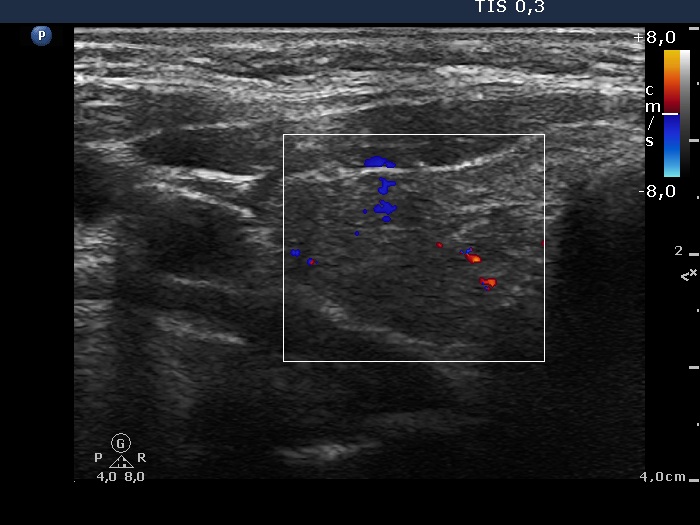

Second examination 7 years later (second row of images):

Clinical presentation. In the past 7 years, the patient had no complaints and therefore did not come to the proposed checkup either. Now he felt it was time to do an investigation.

Functional state: subclinical hypothyroidism with TSH 5.82 mIU/L, aTPO 98 U/mL.

Palpation: a hard nodule in the left lobe.

Ultrasonography. The presentation of the thyroid was essentially the same as 7 years ago. The only discrepancy was the lesion in the left lobe. Firstly, the size of the lesion have substantially increased to 25x18x25 mm (width, depth, and length, respectively), the volume was 5.89 mL which means that the volume became almost 8-times larger. Secondly, it was no more question whether the lesion was a pathological nodule or not. It turned out that this lesion is clearly a pathological nodule. Thirdly, in contrast to the former examination, the nodule has numerous microcalcifications and showed a clearly irregular, lobulated margins.

Aspiration cytology resulted in suspicion of papillary cancer.

Total thyroidectomy was performed, histopathology disclosed a T2 papillary cancer and Hashimoto's thyroiditis.